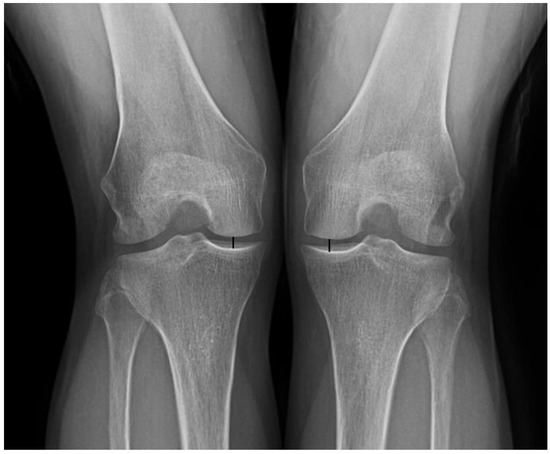

The extent to which resection of unstable leaf should be performed in horizontal cleavage meniscus tear has not yet been elucidated. The purpose of this study was to compare the clinical outcomes of partial meniscectomy for horizontal cleavage tear of medial meniscus between [...] Read more.

The extent to which resection of unstable leaf should be performed in horizontal cleavage meniscus tear has not yet been elucidated. The purpose of this study was to compare the clinical outcomes of partial meniscectomy for horizontal cleavage tear of medial meniscus between complete resection of inferior leaf including the periphery up to the joint capsule and partial resection leaving stable peripheral torn meniscal tissue. A total of 126 patients who underwent partial meniscectomy for horizontal cleavage tear of medial meniscus were divided into two groups: group C (n = 34), treated with the complete resection of the inferior leaf; and group P (n = 92), treated with partial resection of the inferior leaf. The minimum follow-up duration was 3 years. Functional outcomes were evaluated using the Lysholm knee scoring scale, International Knee Documentation Committee (IKDC) subjective knee evaluation form, and knee injury and osteoarthritis outcome score (KOOS). Radiologic assessments were performed using the IKDC radiographic assessment scale and measurement of the height of the joint space in the medial compartment of the tibiofemoral joint. The functional outcomes including the Lysholm knee, IKDC subjective score, activities of daily living and sport and recreation subscale of KOOS were worse in group C than in group P (p < 0.001). The radiologic outcomes including postoperative IKDC radiographic scale (p = 0.003) and the postoperative joint space on the affected side (p < 0.001) were also worse in group C than in group P. In the horizontal cleavage tear of medial meniscus, complete resection of the inferior leaf including the periphery up to the joint capsule showed inferior clinical outcomes compared with partial resection leaving stable peripheral rim of torn meniscus at minimum 3-year follow-up. If the peripheral part of the inferior leaf is stable in horizontal cleavage tear of medial meniscus, partial resection of the inferior leaf preserving peripheral rim can be recommended. Full article